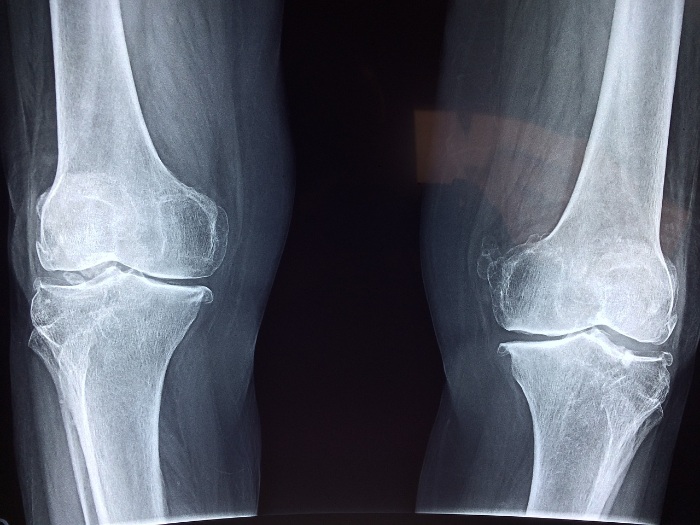

무릎 관절염 자가진단표

※ 3가지 이상 해당된다면 무릎관절염을 의심해야한다.

👉 퇴행성 관절염Osteoarthritis of knee 노화로만 생각하시나요?